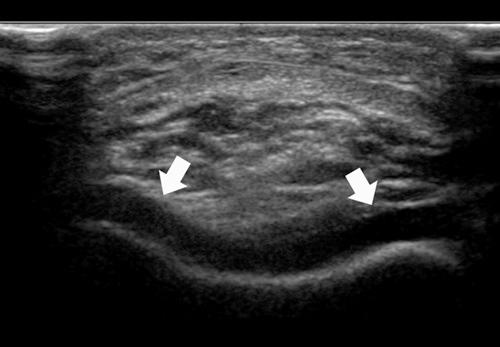

Physical examination and imaging evaluation including standard radiographs are crucial in identifying evidence of malalignment or instability. Magnetic resonance imaging provides valuable information about concomitant soft tissue injuries to the medial stabilizers as well as injuries to the articular cartilage, including chondral shears and osteochondral fractures. Quantitative magnetic resonance imaging assessing the ultrastructure of cartilage has shown high correlation with histology and may be useful for timing surgery.

Evaluation of patellofemoral disorders is complex and requires a comprehensive assessment. Recent advancements in imaging have made possible a more precise evaluation of the individual anatomy of the patient, addressing issues of malalignment, instability, and underlying cartilage damage.